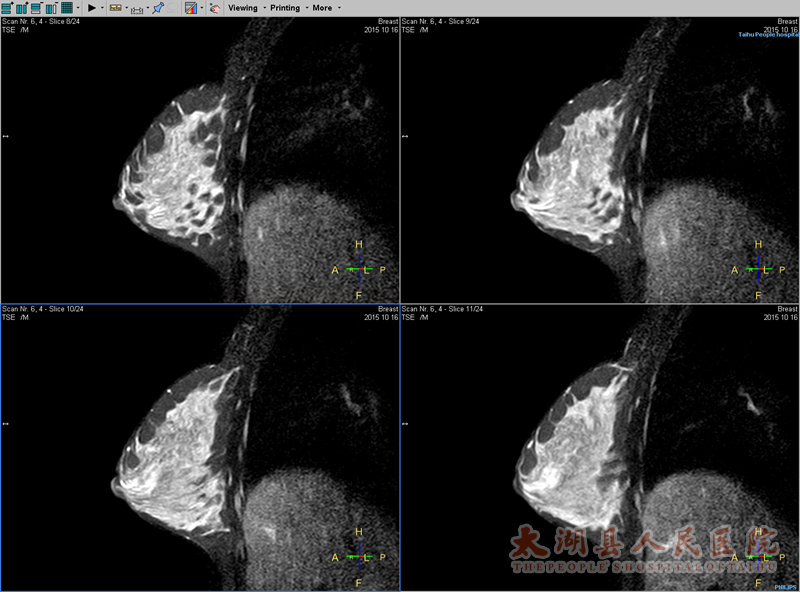

乳腺多系列平扫及功能成像TIWIT2WIT2WISPAIRDWIADC